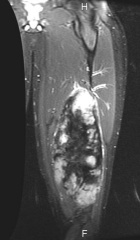

J.G. - 14 year old male c/o left posterior thigh mass for eight months. His mother noticed the mass, but no ecchymosis, after he fell while running hurdles. He complains of pain only when running long distances, and with prolonged pressure. It has decreased in size only minimally. No F/C.